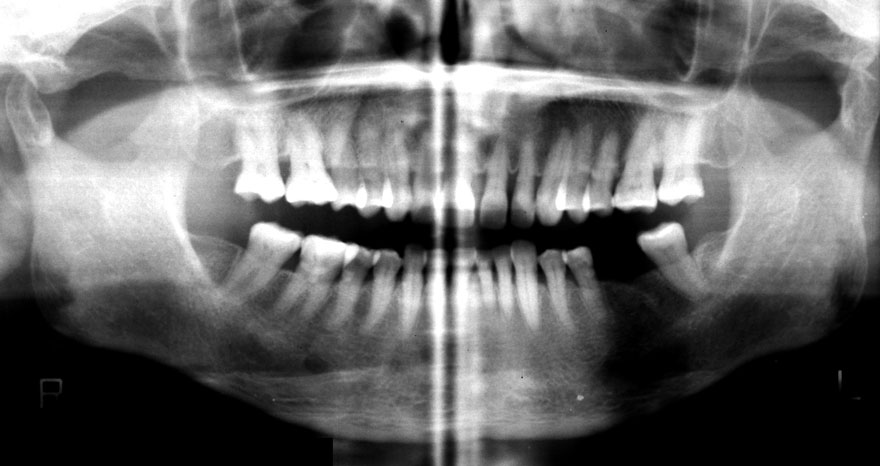

初診時 41歳 男性 平均歯槽骨喪失量:4.11mm

30年後 71歳

平均歯槽骨喪失量:3.70mm

30年間再生量:+0.41mm

年間再生速度:+0.014mm

(ケア頻度:1.27ヵ月ごと)